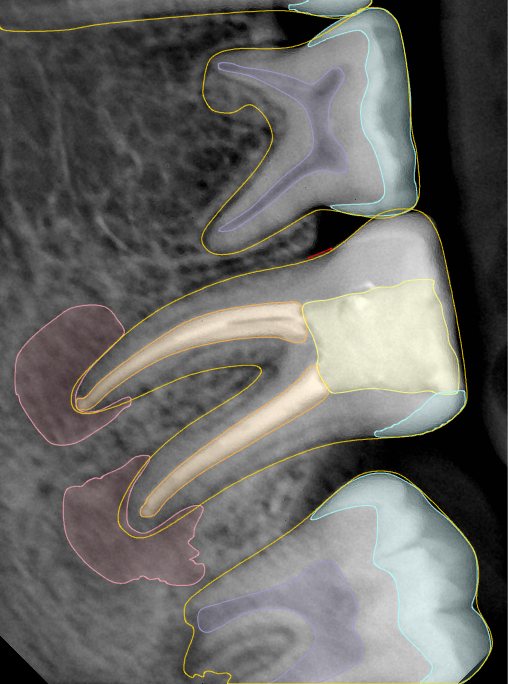

第二版算法问题测试

Updated: 2026-04-13(更新日期)

| 第一版 | 第二版 | 是否解决 | |

|---|---|---|---|

![]() | ![]() ![]() 边角识别有问题 龋齿识别不全 牙髓识别不全 | ![]() | 解决 |

![]() | ![]() 边角识别有问题 识别信息有误 自查(牙冠识别不全) | ![]() | 解决 |

![]() | ![]() ![]() 边角识别有误 大范围填充识别遗漏 | ![]() | 解决 |

![]() | ![]() 识别信息不全 | ![]() | 解决 |

![]() | ![]() ![]() 边角问题 牙胶识别不全 牙冠识别不全 | ![]() | 解决 |

![]() 换图片 | ![]() | ![]() 牙冠部分稍微白了一些就识别成小范围修补,部分判断异常 | 部分解决,修复类略敏感,牙冠部分稍微白了一些就识别成小范围修补,部分判断异常。 |

![]() | ![]() ![]() 牙冠识别不全 牙髓不全 根尖炎龋齿识别有误 | ![]() | 解决 |

![]() | ![]() | ![]() | 解决 |

![]() 换图片 | ![]() | ![]() | 解决 |

![]() | ![]() 牙冠识别有误 | ![]() | 解决 |

![]() 换图片 | ![]() ![]() 边角识别有误 | ![]() 修复类敏感 | 部分解决,图像过白,导致修复类判断异常。 |

![]() 换图片 | ![]() 牙冠识别不全 | ![]() 修复类敏感 | 部分解决,图像过白,导致修复类判断异常 |

结论:修复类出现了不鲁棒的情况,后续需要加入轮廓的扩充数据进行增强。